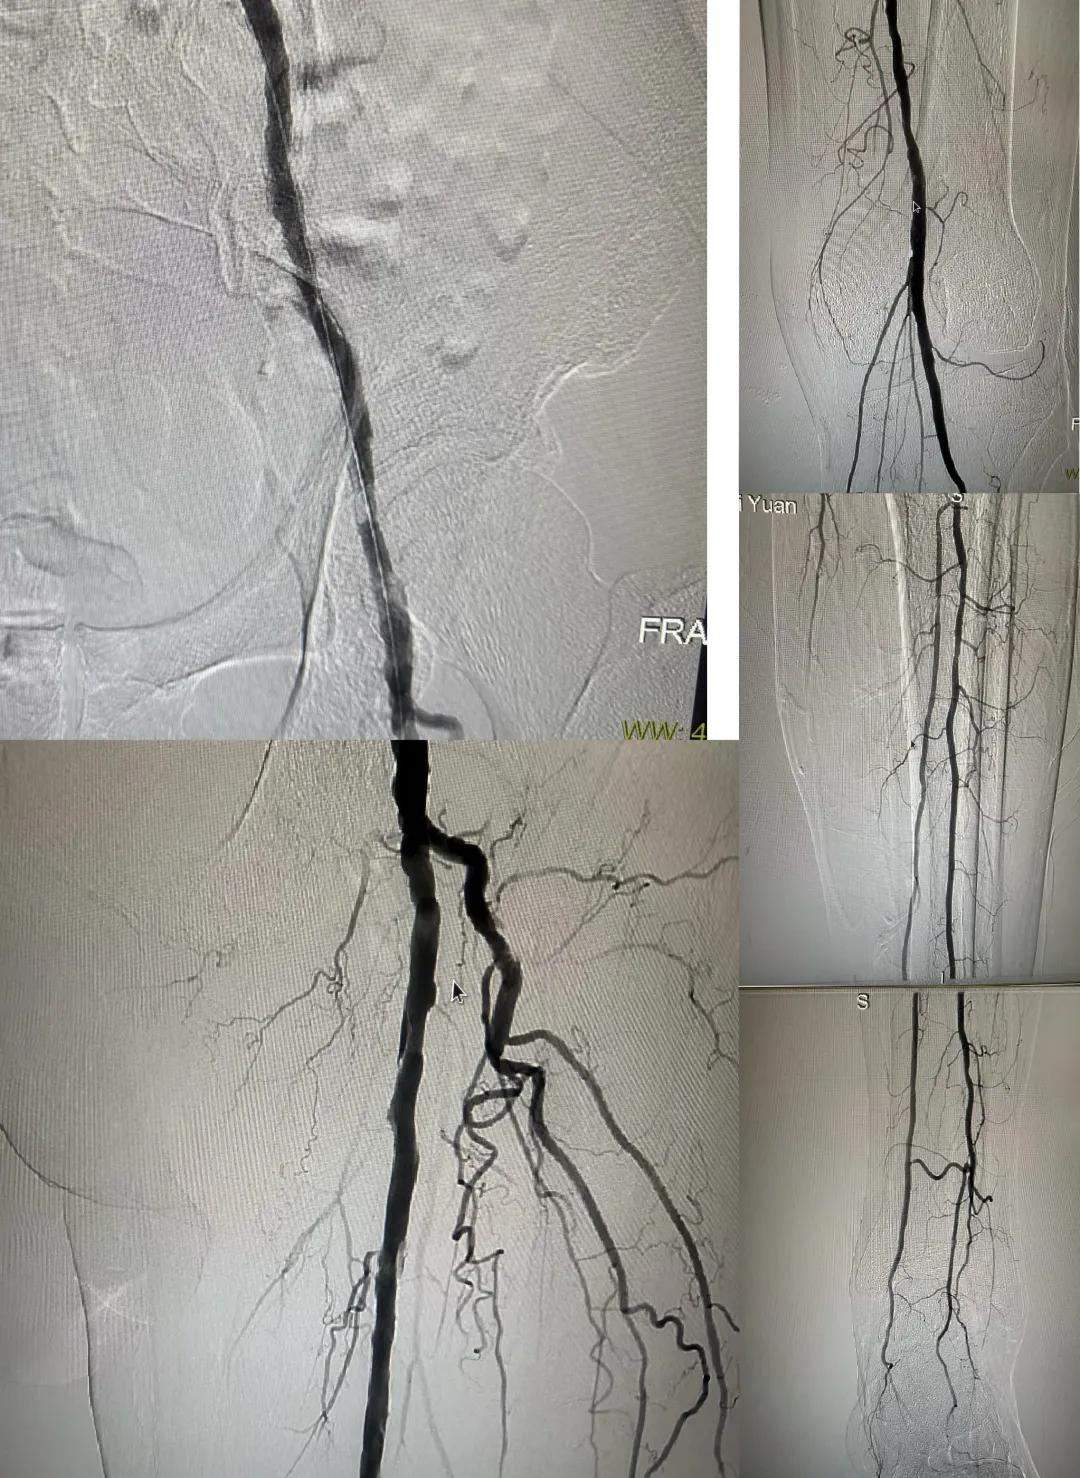

患者,男,73歲,約15天前出現(xiàn)左側(cè)腳面腫痛,間歇性跛行,左足第三足趾壞疽,遂來(lái)市中醫(yī)院就診,以“下肢動(dòng)脈硬化閉塞、糖尿病足壞疽、”收住外二科,評(píng)估患者病情后需實(shí)施左下肢球囊擴(kuò)張成形術(shù)。術(shù)中造影見(jiàn)患者左側(cè)髂動(dòng)脈、股淺動(dòng)脈階段性重度狹窄。經(jīng)外周球囊擴(kuò)張術(shù)后,再次造影見(jiàn)股淺動(dòng)脈、髂動(dòng)脈血流通暢,膝下及足部血流速度較前改善。

術(shù)后已疏通血管成像